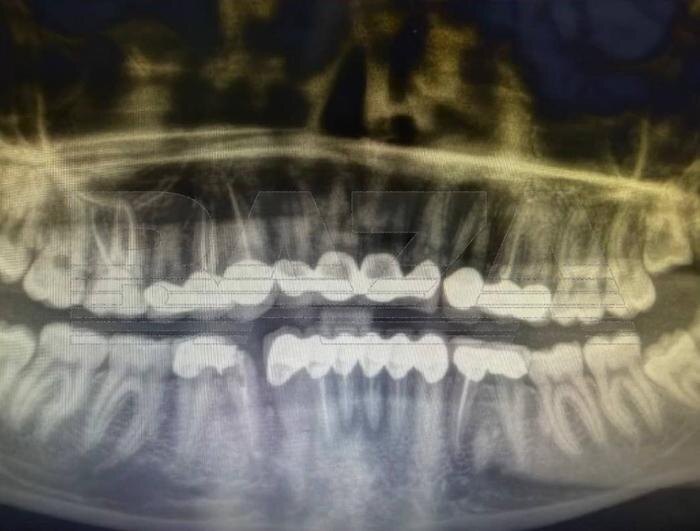

По словам девушки, в марте она обратилась в турецкую клинику для установки виниров. Во время процедуры зубы спилили настолько сильно, что от нижних почти ничего не осталось. Позже пациентка выяснила, что вместо виниров ей фактически установили коронки и мосты на несколько зубов. Уже на следующий день после процедуры появилась сильная боль.

В клинике начали удалять воспалённые нервы — их оказалось целых шесть. Через некоторое время боль вернулась. Таблетки не помогали, поэтому она обратилась в экстренную стоматологию, где врачи обнаружили сильное воспаление и срочно удалили ещё несколько нервов. На следующий день у пациентки сильно опухла щека. Медики предупредили, что инфекция начала распространяться и при более позднем обращении могла потребоваться госпитализация. Кроме того, одна из установленных коронок треснула.